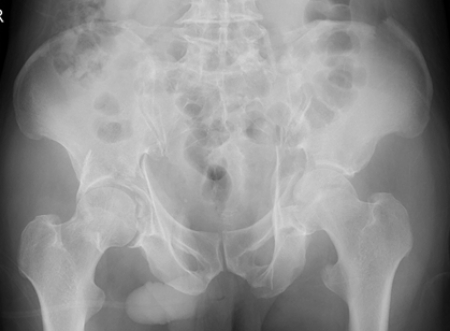

両側寛骨臼骨折 受傷時レントゲン

さらに当科の最大の特徴は整形外傷手術において最も難易度の高いうちの一つとされる骨盤・寛骨臼骨折治療を得意としているところであります。

現在年間50~60件の骨盤・寛骨臼骨折手術を当科で行っており、これは東海地区でもトップクラスであり、近隣の病院からも多くの手術目的の紹介をいただいております。

骨盤・寛骨臼骨折は受傷時に大量出血にて生命を脅かし得る損傷ですがこれに対しても迅速な血管塞栓術の対応が可能となっております。また近年こうした骨盤・寛骨臼骨折の患者様も高齢症例が増加しており内科的合併症が多い場合もございますがこれに対しても内科系救急医と協力し患者様に最善の治療を提供させていただいております。